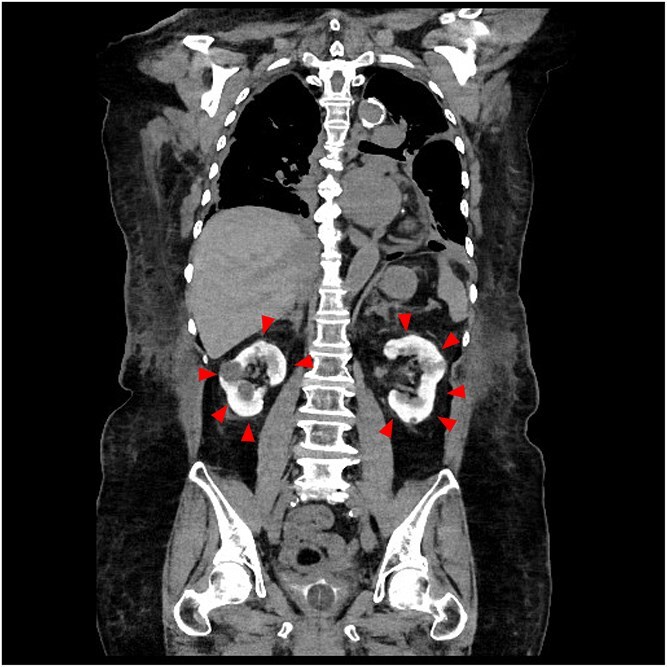

亮肾:经皮冠状动脉介入治疗后造影剂肾病的征象。

Bright kidney: a sign of contrast induced nephropathy after percutaneous coronary intervention.